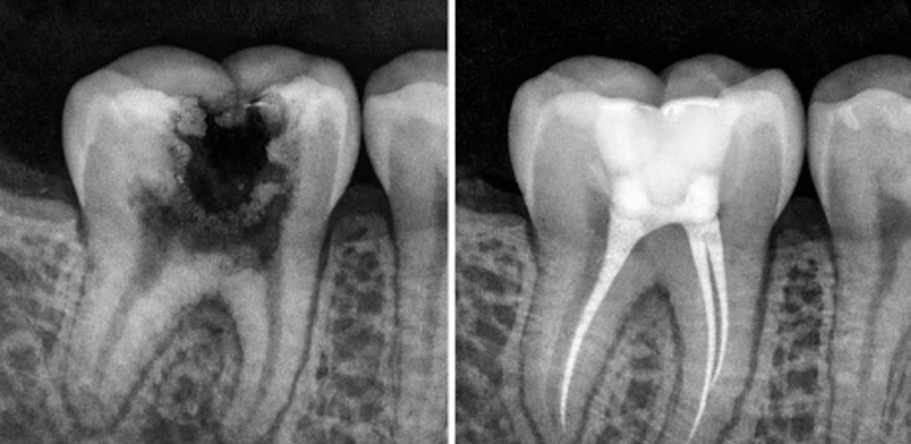

Es un procedimiento dental diseñado para tratar infecciones o daños dentro de un diente. Implica la extracción de la pulpa dental (el tejido blando dentro del diente que contiene nervios y vasos sanguíneos), seguido de la limpieza, desinfección y sellado de los conductos radiculares. Este tratamiento es recomendado cuando la caries esta cerca del nervio y es necesario cuando la pulpa se daña o se infecta a causa de caries profundas, su objetivo es salvar el diente y prevenir su extracción.

• Caries severas

La infección puede empeorar y propagarse al hueso circundante u otras partes del cuerpo.

Retrasar el tratamiento puede llevar a procedimientos más costosos y complejos, como implantes o puentes.